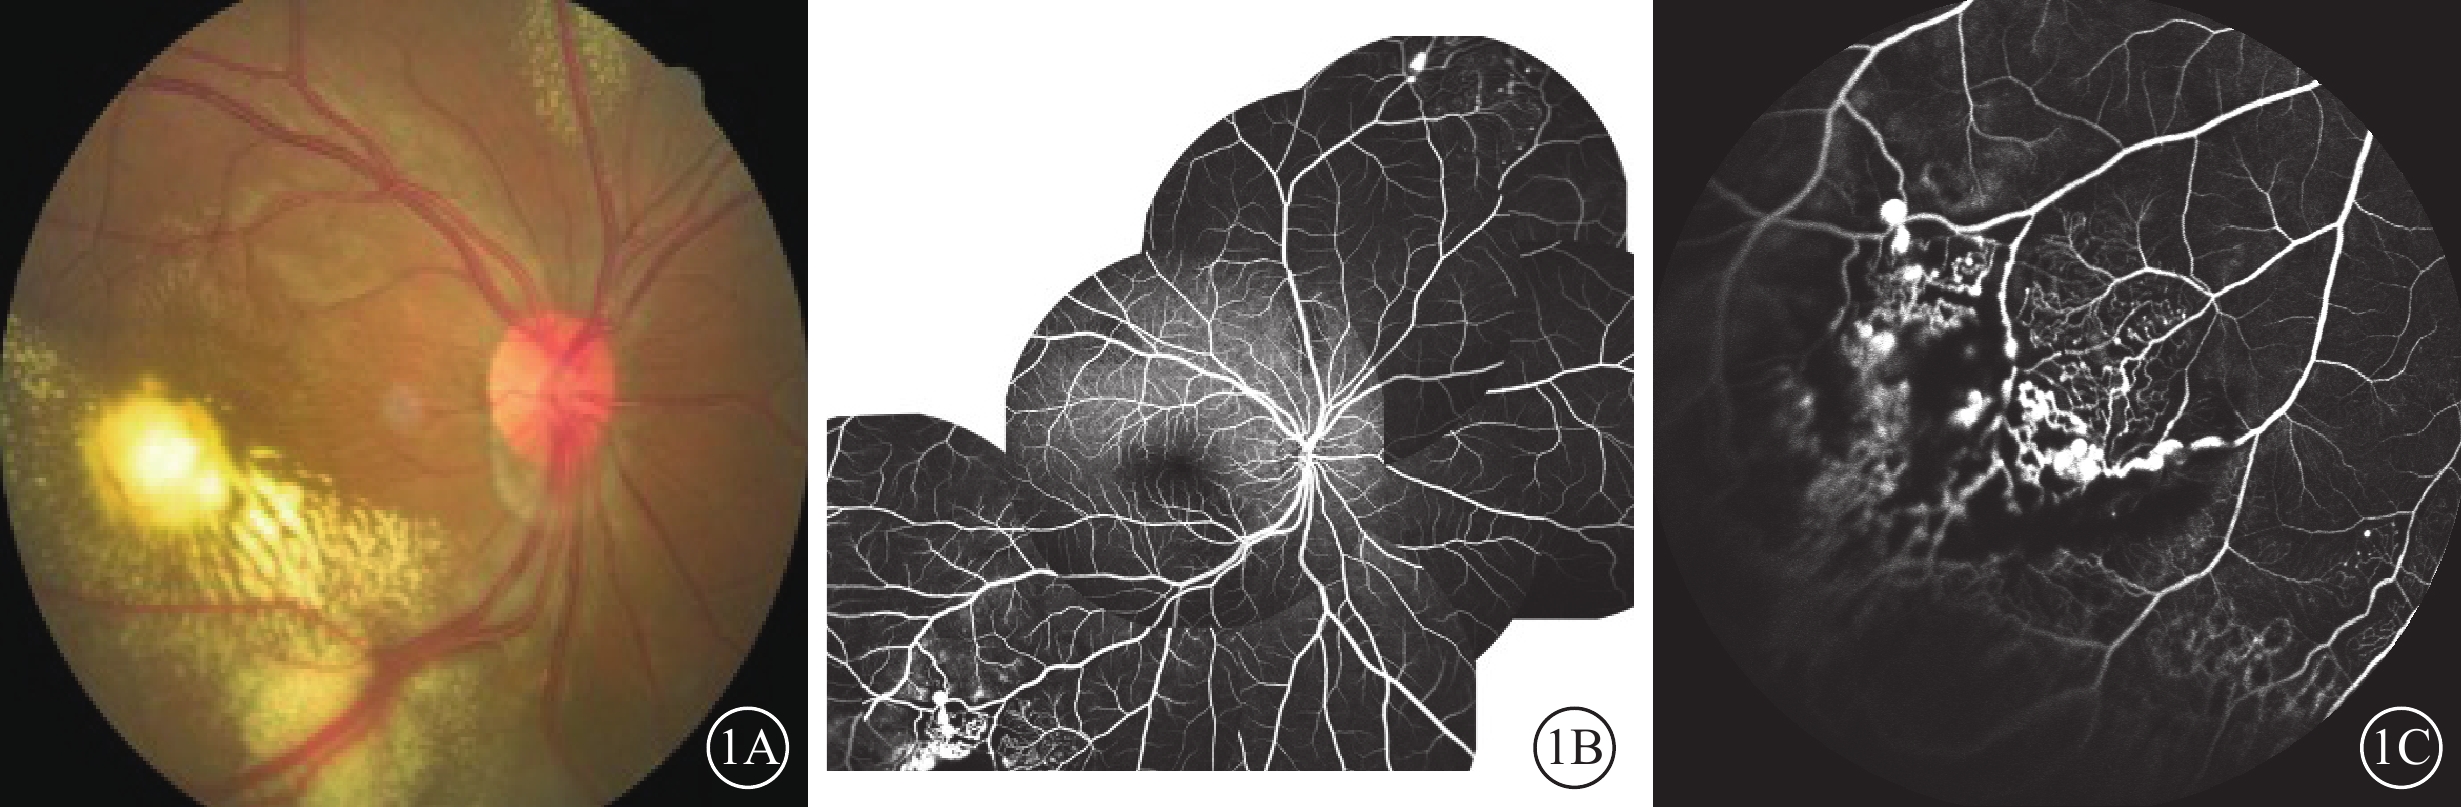

48例患者中,男性40例40只眼,女性8例8只眼;平均年齡(32.46±22.41)歲。患眼BCVA≤0.32 logMAR單位者(小數記錄≥0.5)12只眼(25.00%,12/48)。2A期9只眼,平均logMAR BCVA為0.26±0.32;2B期39只眼,平均logMAR BCVA為0.92±0.52。所有患眼均可見異常擴張視網膜血管及視網膜層間及視網膜下滲出(圖1A);FFA檢查,顳下及鼻上周邊視網膜可見異常擴張的毛細血管及血管瘤(圖1B,1C)。

圖1

Coats病患眼局部視網膜激光光凝治療前眼部檢查像。1A示彩色眼底像,后極部硬性滲出累及黃斑;1B、1C分別示熒光素眼底血管造影像,顳下及鼻上周邊視網膜異常擴張的毛細血管及血管瘤(1B)以及顳下周邊病灶(1C)